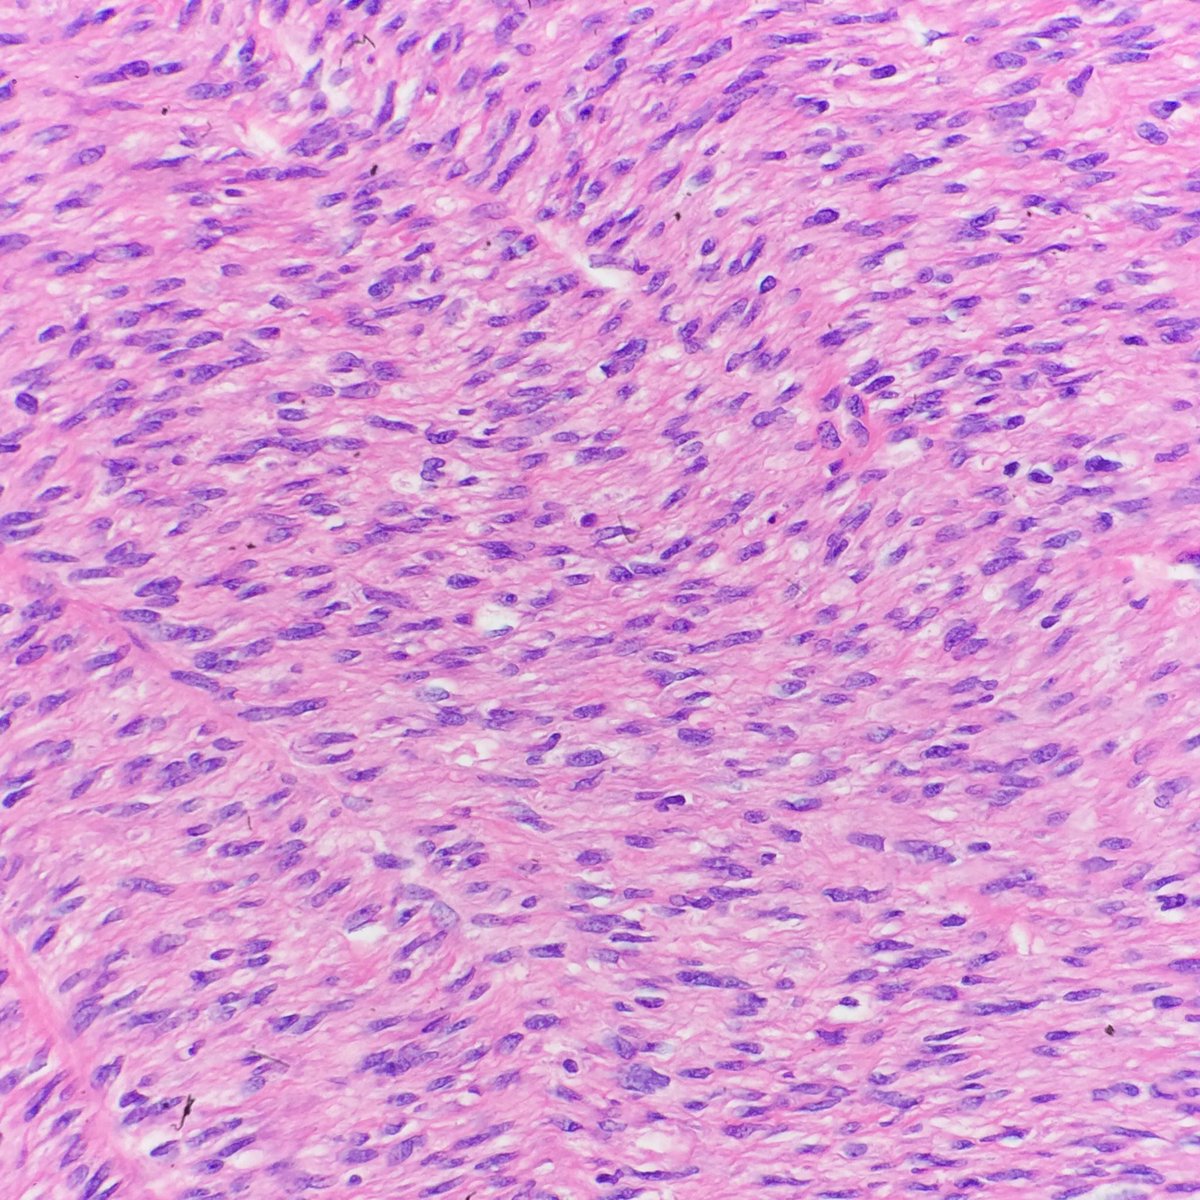

Congenital Mesoblastic Nephroma Pathology

Congenital Mesoblastic Nephroma In A Premature Neonate A Case Report And Review Of Literature Anunobi C C Badmos K B Onyekwelu V I Ikeri N Z Niger J Clin Pract